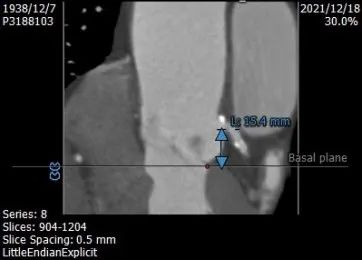

左右冠开口高度:15.4 mm、15.4mm